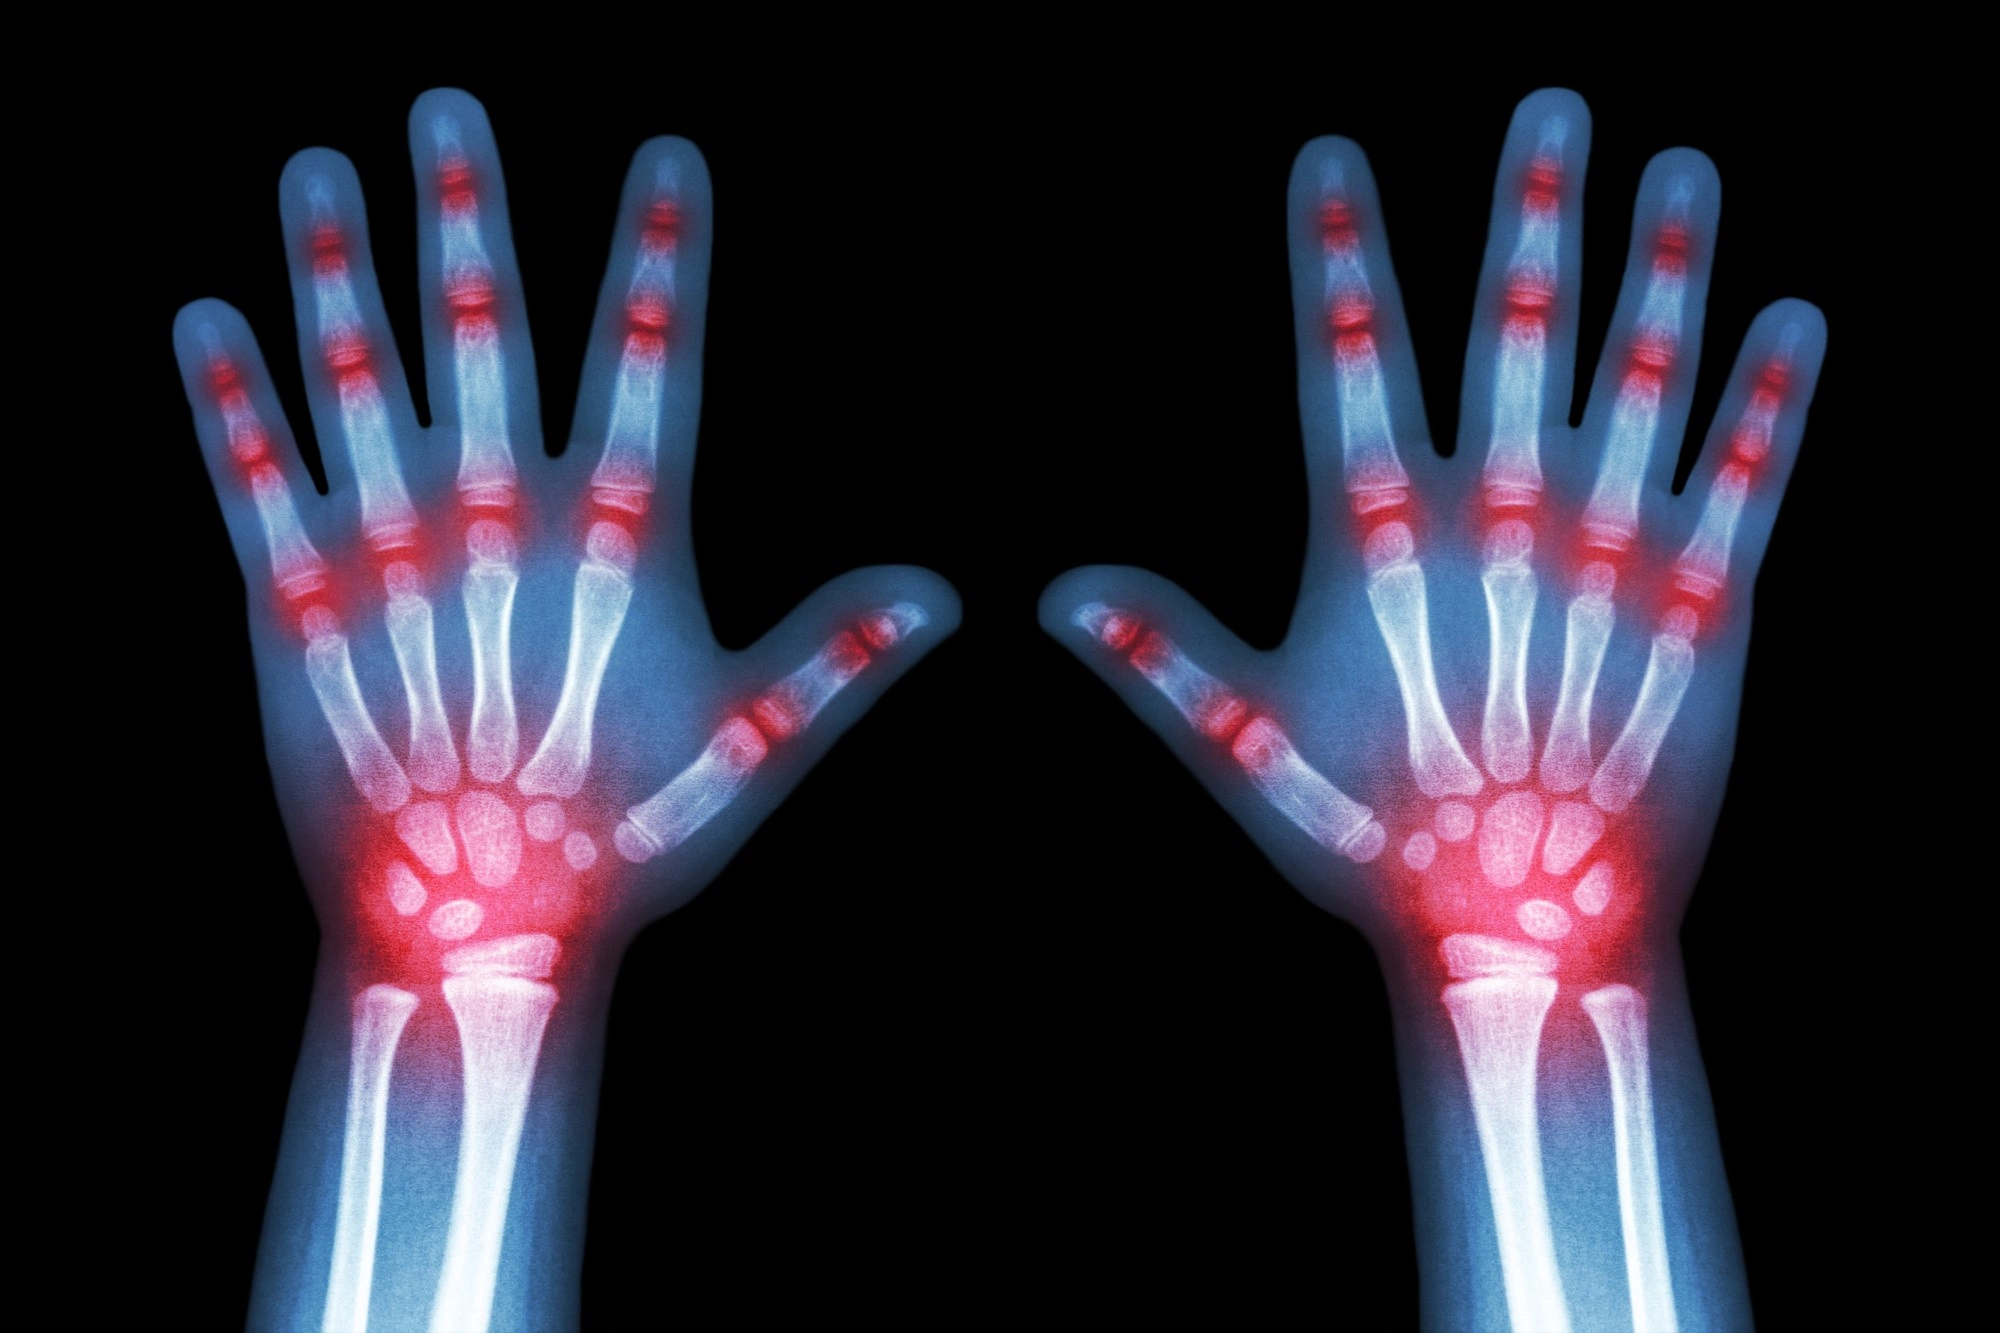

- Боли в суставах.

Задача лечащего врача состоит в купировании, т.е. устранении болевых ощущений и установлении контроля над течением заболевания: даже если невозможно вернуть состояние суставов до поражения, то можно не допустить прогрессирования. Мы предупреждаем своих пациентов о том, что лечение ревматоидного артрита может растянуться на всю жизнь: будут требоваться периодические визиты к врачу для консультации и прохождения курса лечения, которое поддержит состояние суставов в неизменном состоянии. Используются только проверенные, доказавшие свою эффективность методики.

Поэтому используются только проверенные, доказавшие свою эффективность методики. В первую очередь, это лекарственная терапия, которая направлена на скорейшее снятие воспаления в суставах или в организме, если оно успело распространиться на другие органы. Для эффективности лечения некоторые препараты (к примеру, глюкокортикостероидные) вводятся внутрисуставно. Применяются нестероидные противовоспалительные препараты обезболивающие препараты для снятия сильного болевого симптома.